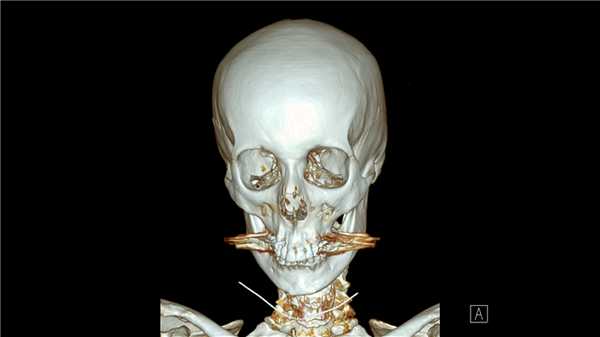

(Слева) На передне-задней рентгенограмме определяются двойной перелом лучевой кости и оскольчатый перелом средней трети диафиза локтевой кости. Обратите внимание, что в то время как дистальные трети костей предплечья и запястья видны в передне-задней проекции, проксимальная треть костей предплечья и локтевой сустав находятся в боковой проекции, что указывает на вращение на 90° в местах переломов.

(Справа) На боковой рентгенограмме у этого же пациента определяются переломы лучевой и локтевой костей со смещением на ширину диафиза. (Слева) На передне-задней рентгенограмме определяется перелом дистальной трети локтевой кости с легким угловым локтевым отклонением дистального отломка перелома. Лучевая кость интактна. В случае, когда перелом возникает в кости предплечья вследствие травмы при прямом ударе, как например, этот, другая кость часто остается интактной.